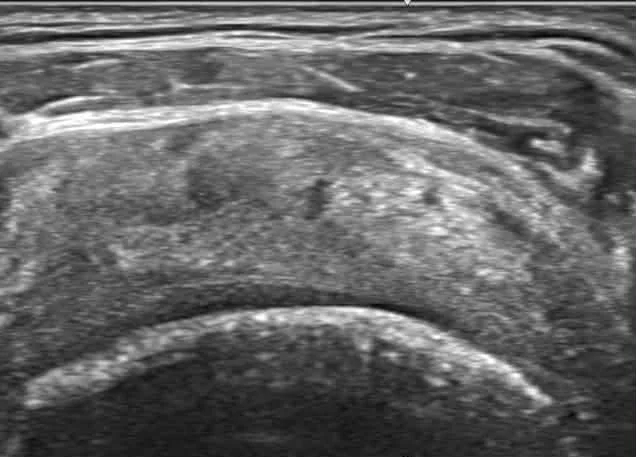

2. 超音波導引:差之毫釐,失之千里

注射位置不精準是失敗主因。我們堅持全程搭配高解析超音波導引,確保藥物精準打到患部撕裂處,這才是決定療效的最後一哩路。

💉 超音波導引:精準醫療的靈魂

在宸新復健科,我們堅持「眼見為憑」。醫師能將針頭精準引導至病灶核心,大幅提升治療成功率並減少疼痛。研究指出,超音波導引可確保 PRP 精準送達目標組織,是影響治療結果的關鍵因素[14]。